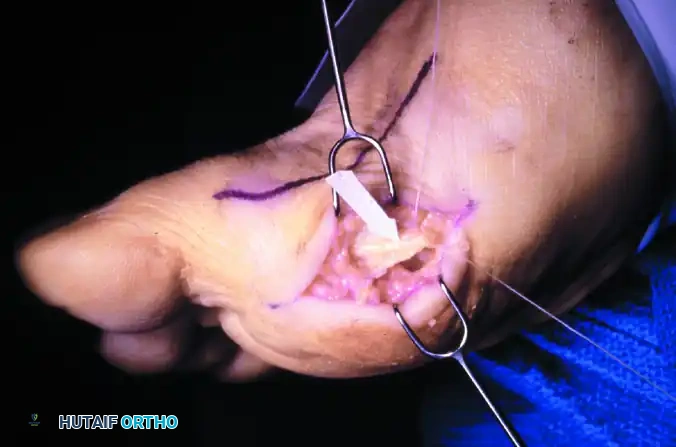

FIGURE 81-110B: The arrow and suture delineate the proper digital nerve to the medial side of the hallux. The nerve intimately blends with the capsule and subcutaneous tissue, making it highly vulnerable by both position and appearance during a plantar approach.